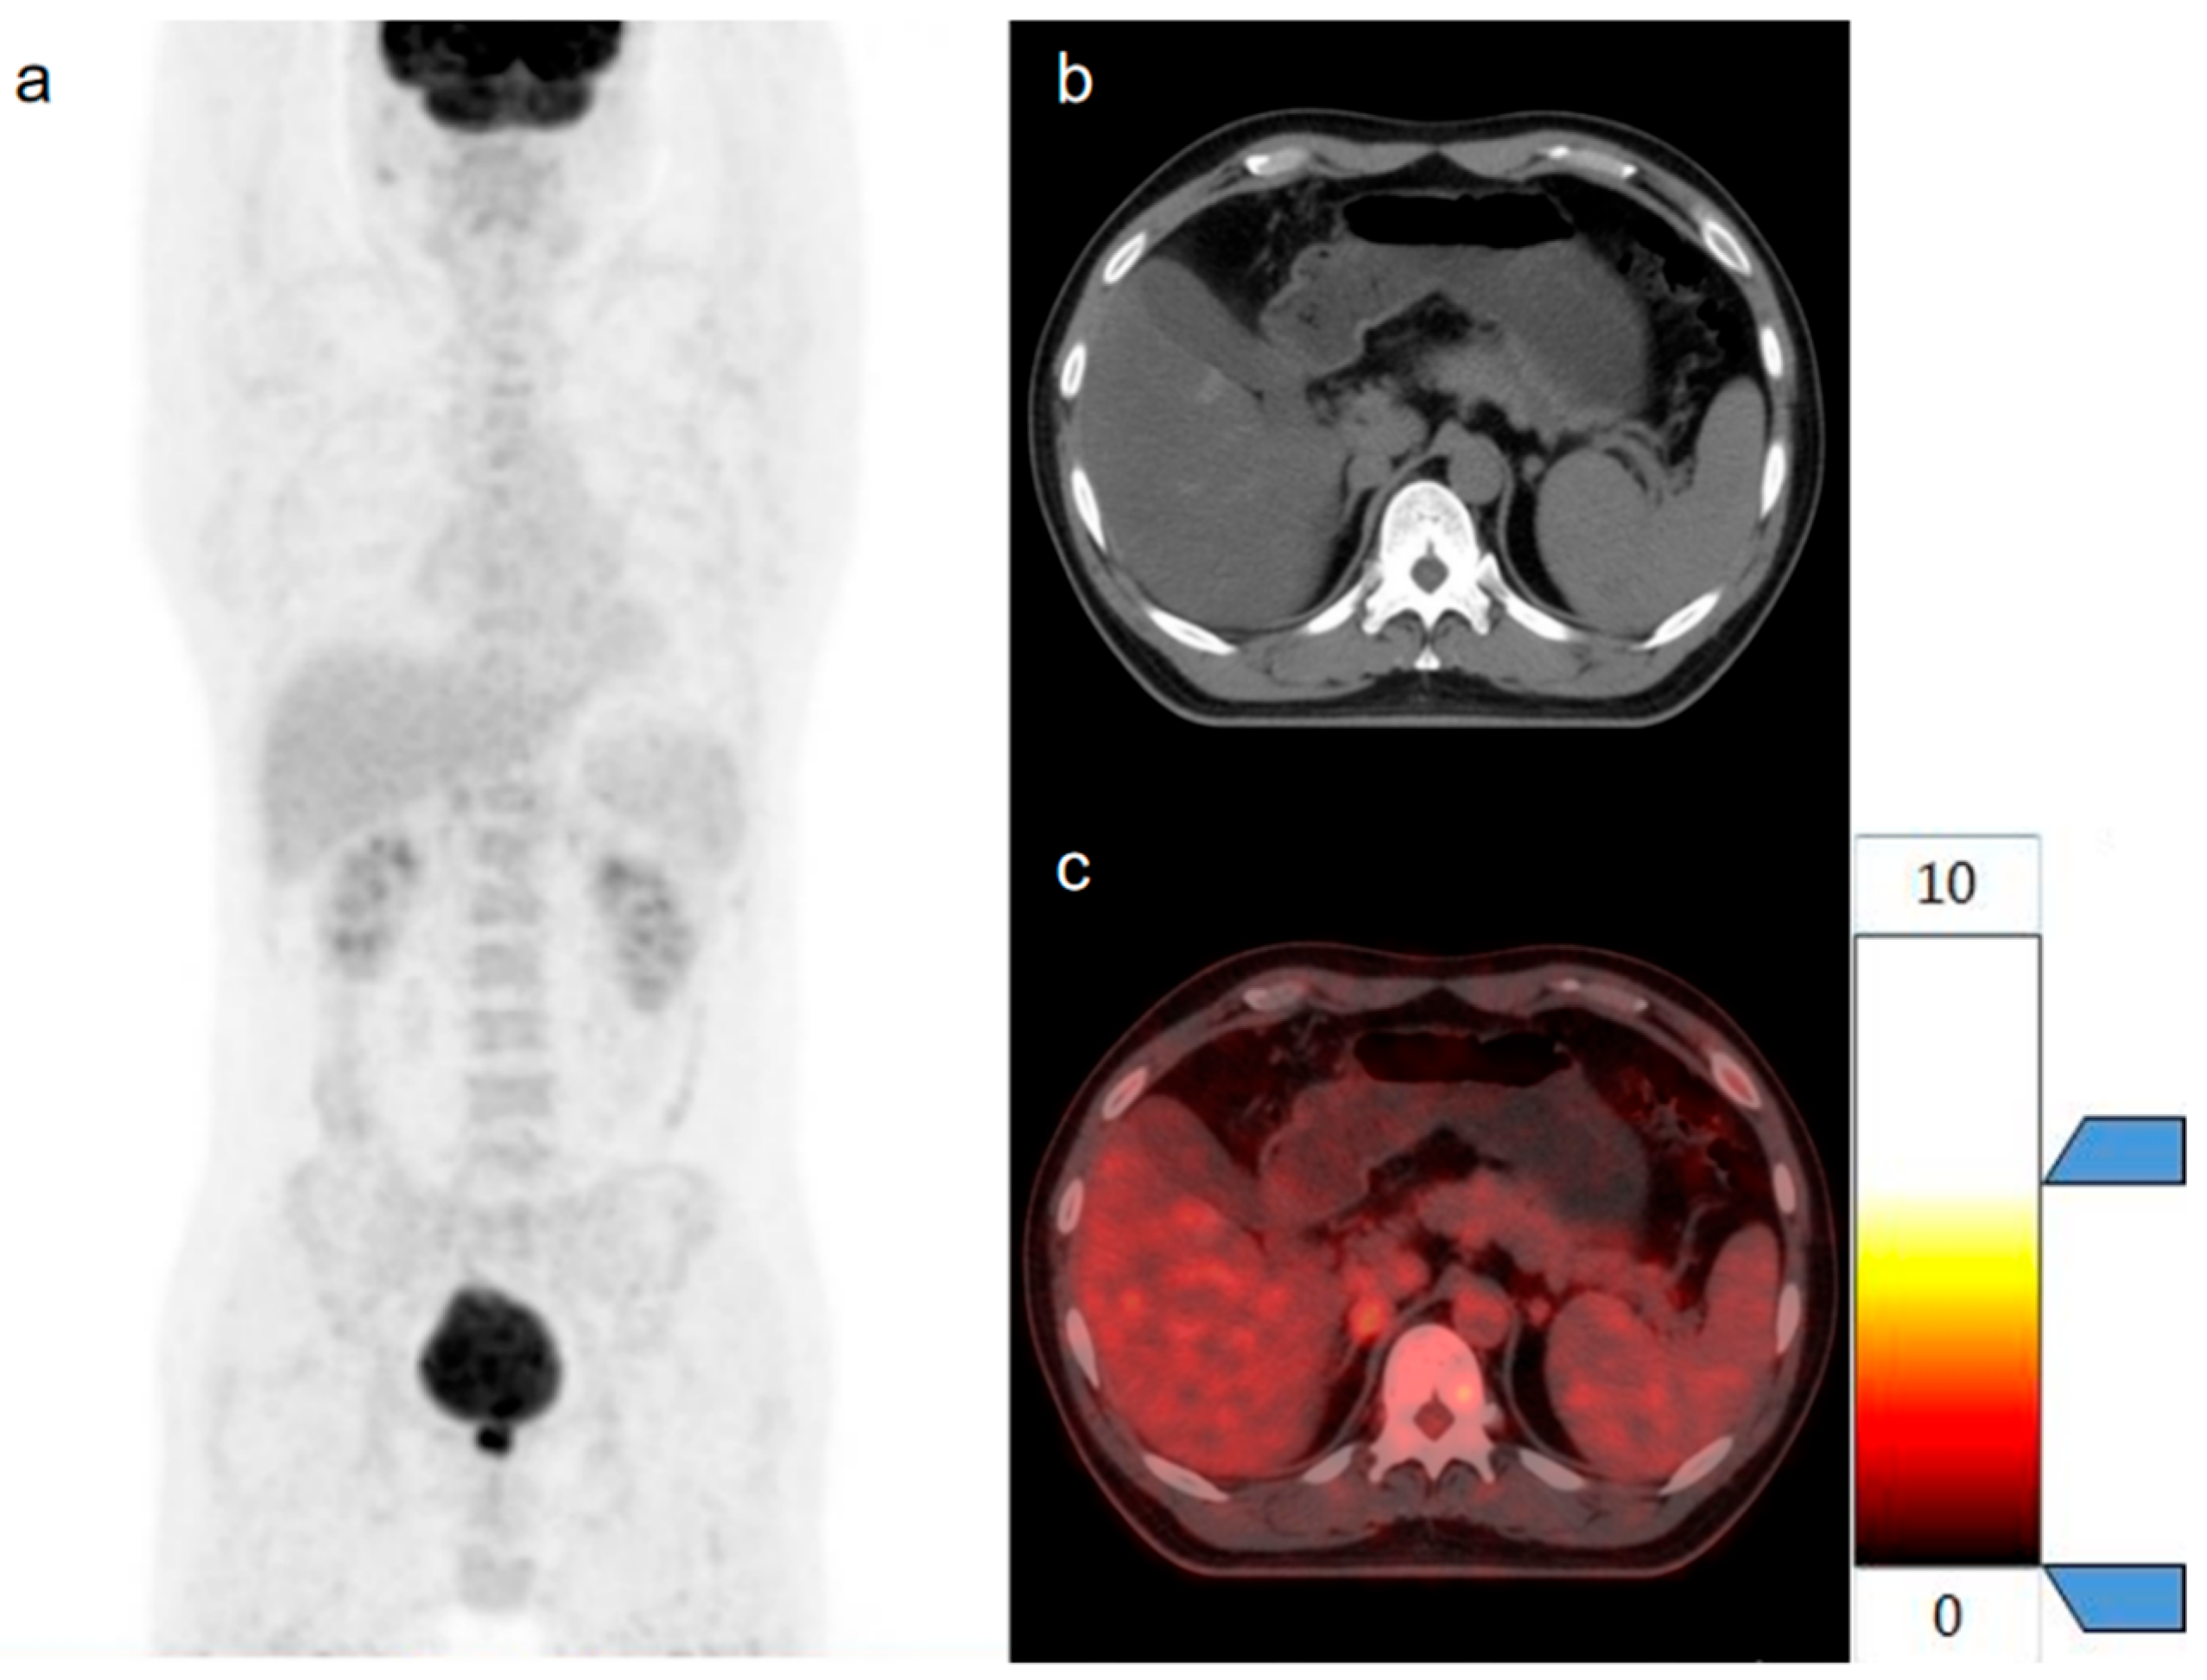

2.5. Three-Dimensional Segmentation